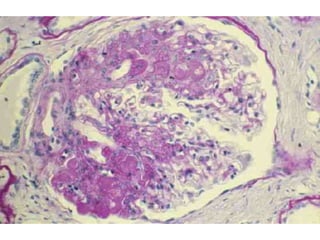

CLASIFICACIÓN

• Histológica

– Lesiones glomerulares mínimas

– Proliferación mesangial difusa

– Glomeruloesclerosis focal y segmentaria

– Glomerulonefritis membranosa

– Glomerulonefritis membranoproliferativa

– Glomerulonefritis endocapilar y extracapilar

difusa